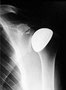

An der Schulter stehen sehr unterschiedliche Implantate zur Verfügung. Man muss abwägen, ob die Muskelfunktion noch intakt ist oder nicht. Entsprechend kommen sehr unterschiedliche Prothesentypen zum Einsatz. Unter Umständen sind aufwendige Voruntersuchungen wie Computertomographie oder Kernspintomographie notwendig, um für Sie die optimale Prothese auszuwählen.